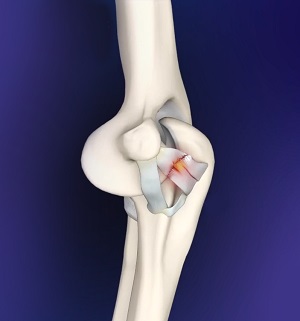

Ulnar Collateral Ligament (UCL) Injury

The ulnar collateral ligament (UCL), also called the medial collateral ligament, is located on the inside of the elbow...